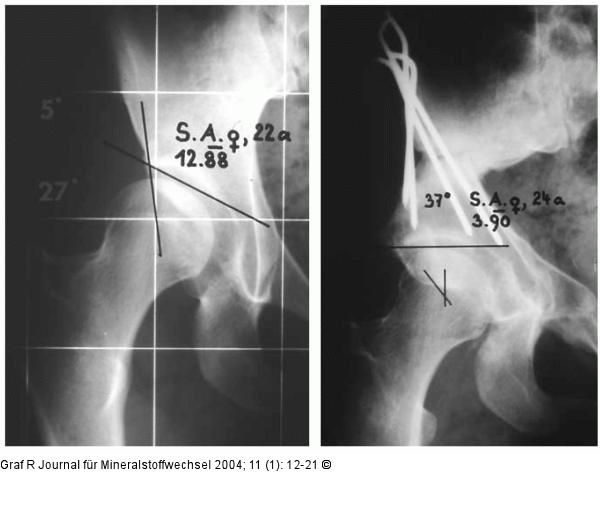

Abbildung 12: Hüftgelenk Schwere Pfannendachdysplasie bei einem 22jährigen. Korrektur durch eine Triple-Osteotomie. 2 Jahre postoperativ. |

Abbildung 12: Hüftgelenk

Schwere Pfannendachdysplasie bei einem 22jährigen. Korrektur durch eine Triple-Osteotomie. 2 Jahre postoperativ. |